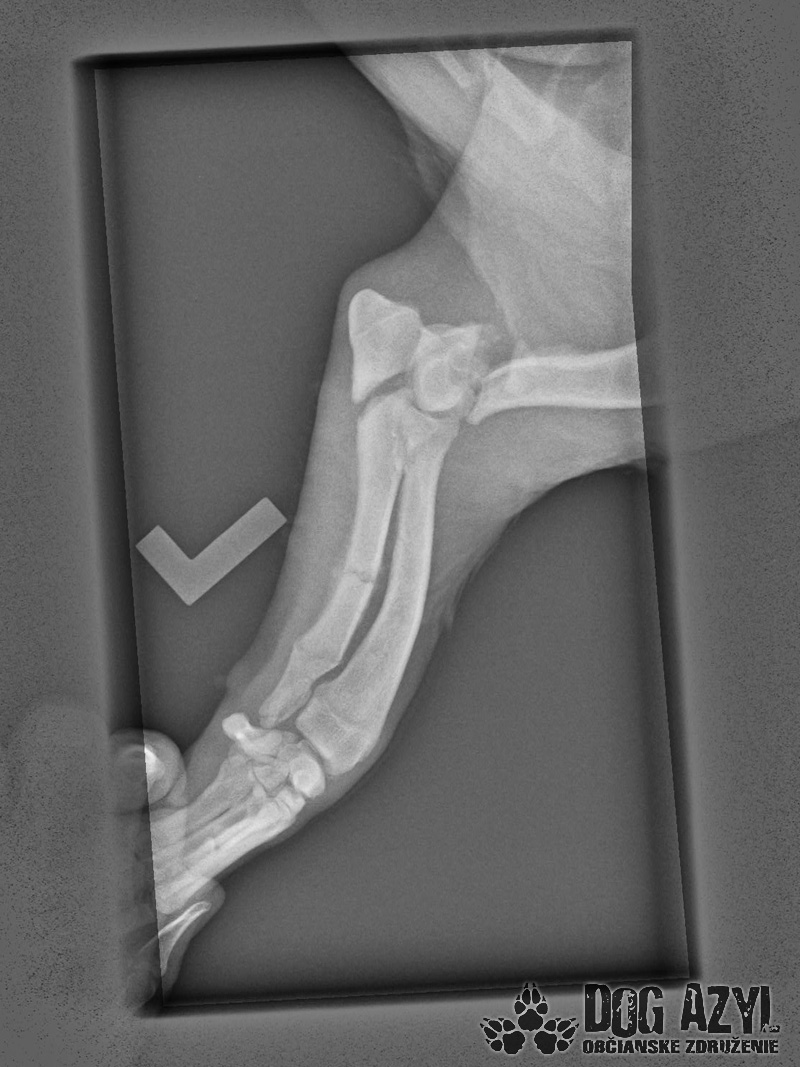

Išli sme najprv na RTG, celú dobu sa nechal polohovať a pozeral nám pri tom do očí, zmierený s osudom, zrejme si povedal, že viac, ako to bolí, to už bolieť nebude.

Z prvých snímkov je viditeľné, že má zlomený lakeť ľavej prednej nohy a aj kosti tam má polámané, takisto má zlomenú ľavú zadnú nohu, panva zatiaľ zlomeninu neukázala, ale uvidí sa pri podrobnejšom vyšetrení v pondelok, kedy pôjde na operáciu. Faktom však je, že to nebolo úplne čerstvé zranenie, takže v tej priekope ležal už niekoľko dní, ten, čo ho zrazil, ho tam bezcitne nechal napospas osudu a Skip v bolestiach čakal na smrť.